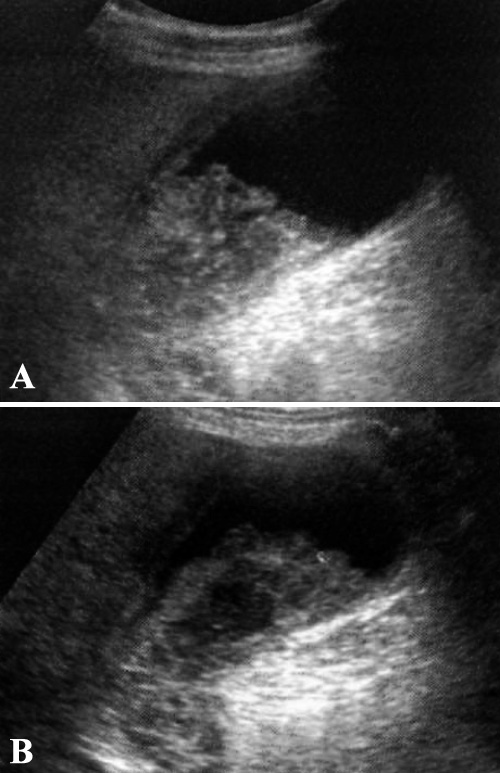

Застойная желчь формируется из билирубината кальция и кристаллов холестерина, которые содержаться в желчи. Ультразвуковая картина застойной желчи характеризуется эхом умеренной интенсивности. Застой желчи, обусловленный перееданием, обструкцией желчевыводящих протоков на уровне желчного пузыря, пузырного протока или общего желчного протока, является основной причиной образования застойной желчи (фото 10). Застой желчи (билиарный сладж) может указывать на какое-либо сопутствующее заболевание, однако не является специфическим признаком.

Фото 10. Застой желчи (билиарный сладж). А – УЗИ в продольной проекции, пациент в положении лежа на спине. В – УЗИ в продольной проекции того же пациента в положении лежа на левом боку. Ультразвуковая картина демонстрирует подвижный эхогенный застой желчи, форма которого меняется при перемене положения тела пациента